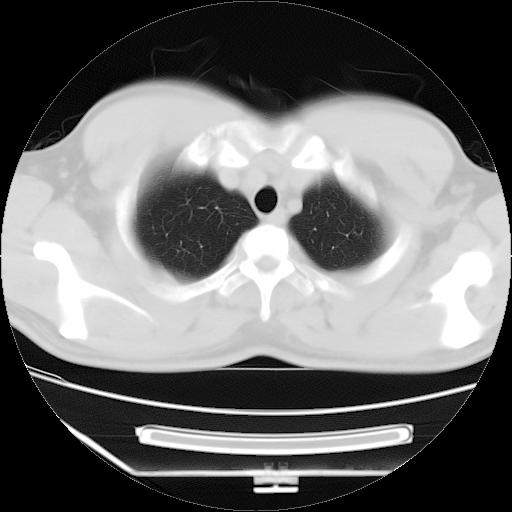

男,38岁,于2009年8月9日晚突发左侧胸痛,今x线提示左下肺阴影,为了明显确诊断,行ct检查,

血常规:嗜酸性细胞增高,单核细胞增高。

病灶发生在下叶,密度均匀,边缘模糊、毛糙,周围血管纹理增强扭曲改变,靠近胸膜处病灶胸膜反应明显。

支持考虑---球形肺炎。

左肺舌叶病变。主体病灶呈类圆形中心密度低,成液化趋势周边班片影分布

考虑肺脓肿